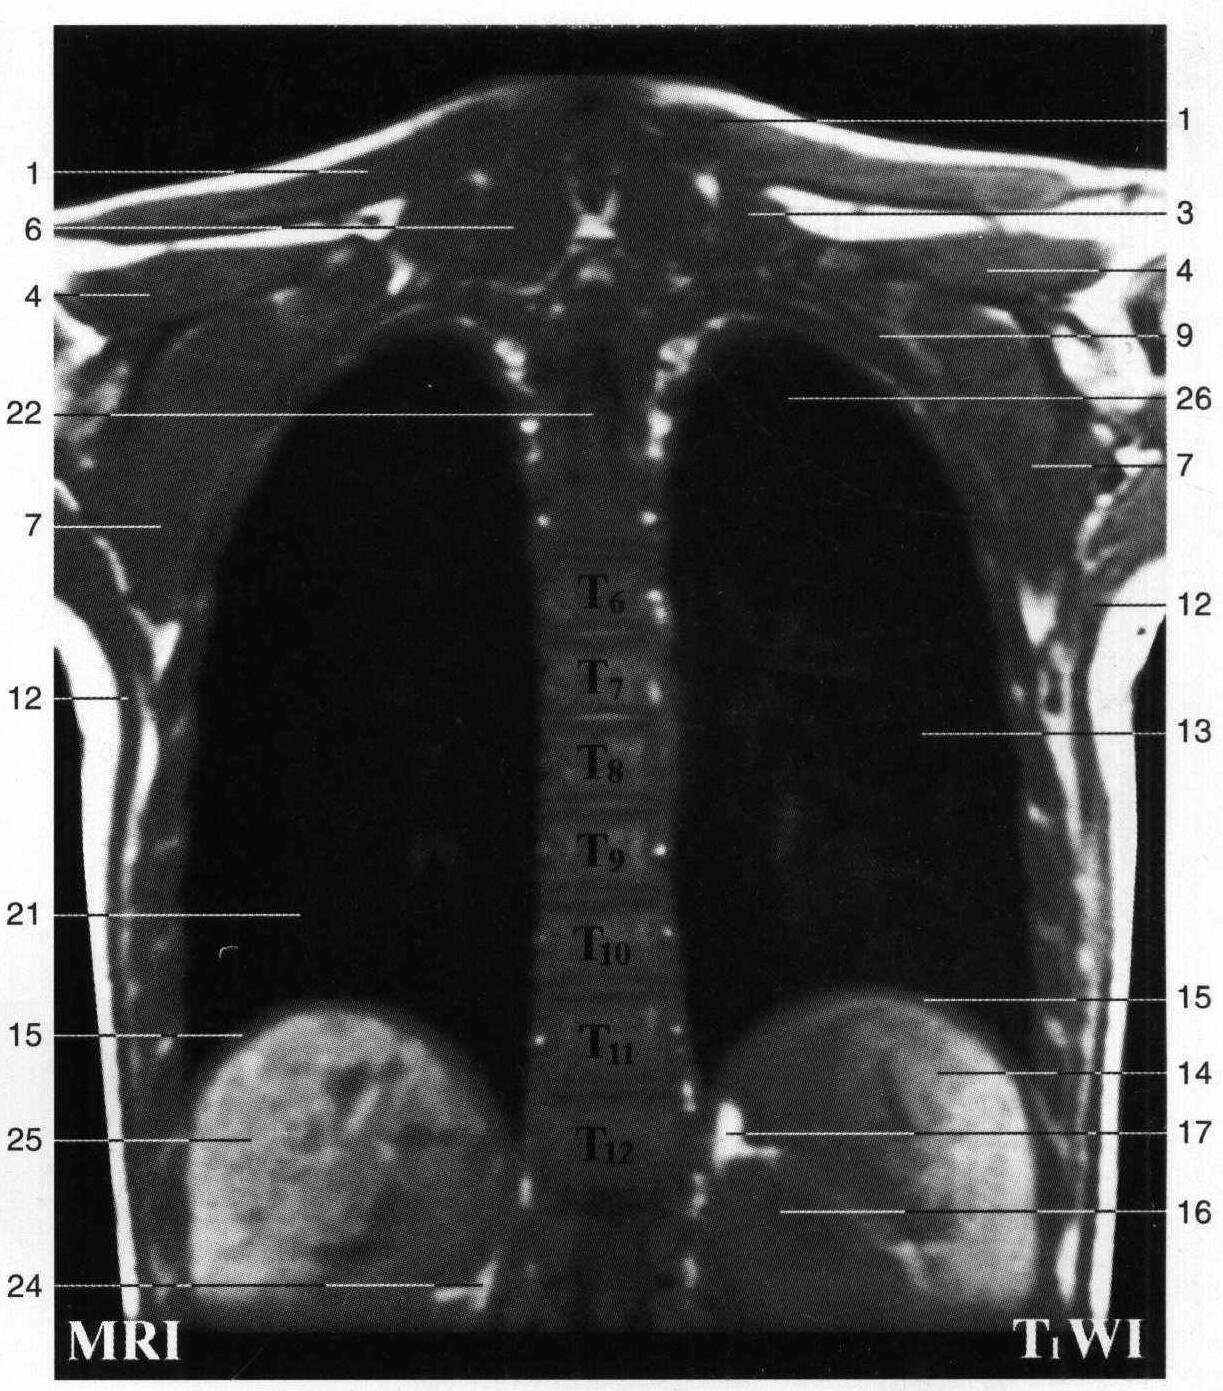

断面解剖与mri ct ect对照图谱_知网百科

人体断层影像解剖学

医学 ct与mri影像解剖学 正文 1. 股直肌rectus femoris 2.